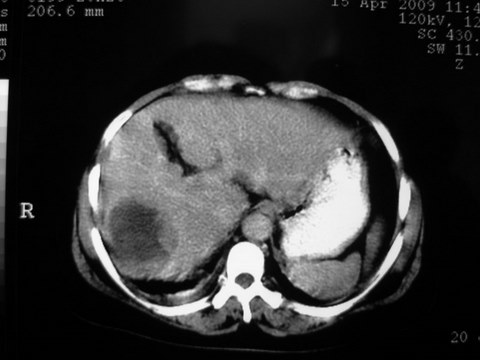

患者 女 51岁 两天前感觉上腹疼,无明显诱因,b超示肝右叶囊实性占位,边缘清楚,其内回声不均匀,ct增强如图,大家看看是什么 ,病人一年前及两月前b超检查只是提示胆囊炎

外院术后,证实肝癌合并出血

特点:1,病灶发展迅速,(2月前正常)[br] 2,囊实性,且并边界清晰光滑,呈右后叶赘生性。囊性区无强化,实性部分较多轻度强化,边界欠清。考虑囊腺癌或囊腺瘤。

出病理 中分化肝细胞癌合并出血